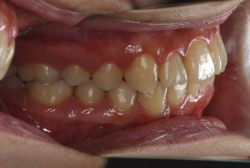

「出っ歯を治したい」という主訴で来院したケースです。診断の結果、「2級1類の上顎前突+軽度叢生」と判明しました。2級というのは、基本的に出っ歯の噛み合わせになっていることを言います。その中でも上の前歯が著しく外に反っているケースを、「1類」といいます。初診時の横向きの写真を見ると、それがはっきり分かります。上の前歯に押されて唇も膨らんで、審美線をかなりオーバーしています(審美線とは、鼻の先端と顎の先端を結ぶ線のことで、この線よりも唇は内側にある方が良いとされています)。

このような症状の場合は、前歯を内側に入れるためにかなり大量の隙間を必要とします。通常は上下左右の小臼歯を抜歯させていただくのが正解です。治療後は歯の角度が正しくなっただけでなく、唇の審美性が大幅に改善しました。もちろん噛み合わせ的にも正しい状態が確立しています。